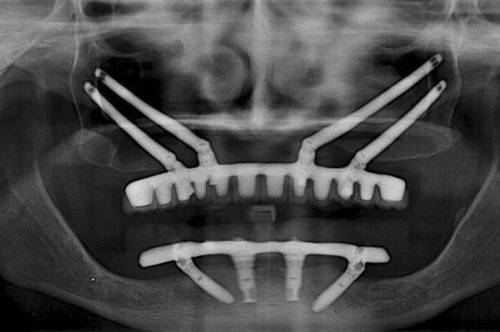

穿顴種植牙是上頜骨嚴(yán)重骨吸收情況下的一種有效替代治療方法,也可被用于上頜骨缺損的修復(fù)治療,既避免了大量的植骨手術(shù),且能明顯縮短種植治療周期。

效果展示

手術(shù)方式

1. 骨量充足的 1 區(qū)及雙側(cè)缺骨的 2、3 區(qū):建議 2-4 顆傳統(tǒng)軸向種植體位于 1 區(qū),雙側(cè) 2 或 3 區(qū)各加一顆顴骨種植體。

2. 骨量充足的 1 區(qū)及一側(cè)缺骨的 2、3 區(qū):建議缺骨側(cè) 2、3 區(qū)一顆顴骨種植體,對側(cè) 2、3 區(qū)及 1 區(qū)采用常規(guī)種植體。

3. 缺骨的 1 區(qū)及骨量充足的 2、3 區(qū):一顆顴骨前種植體加后方常規(guī)種植體即可。

4. 1、2、3 區(qū)均缺骨:4 顆顴骨種植體即可。